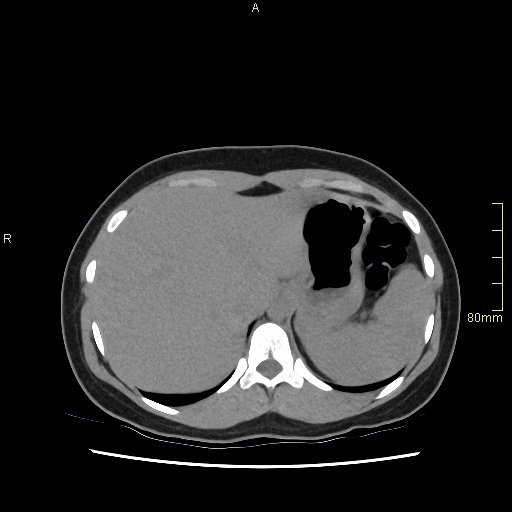

CT Urogram No Contrast (Axial)